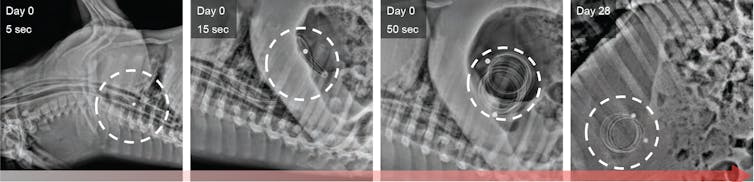

Inspired by the capacity of the stomach to hold large objects such as bariatric balloons, our group at MIT has recently designed a pills-on-a-coil system that can hold and release at least 10 grams of drug for one month. We have tested this in pigs. This system is able to dispense the quantity of antibiotics necessary to treat TB, the world’s leading killer among infectious diseases, for one month. Nonadherence to TB treatment, which requires at least six months of multiple daily pills, is a major reason the treatment fails.

Our pills-on-a-coil system consists of a coiled wire upon which medication is strung, like a candy necklace. The ends of the wire are protected in piece of tube with a magnet. The wire is superelastic and can be stretched to pass through the esophagus and then form a tight coil when it reaches the stomach. Cylindrical drug pills are made from mixing the drug with silicone followed by coating a thin layer of something called Eudragit RS 100. Silicone and Eudragit RS 100 are common materials used in long-term drug delivery to provide slow drug release. All pills simultaneously release a predictable amount of drug into the stomach. Once all drugs from the pills have been released, a separate retrieval device with a magnet can sense, attach and remove the coil from the stomach.